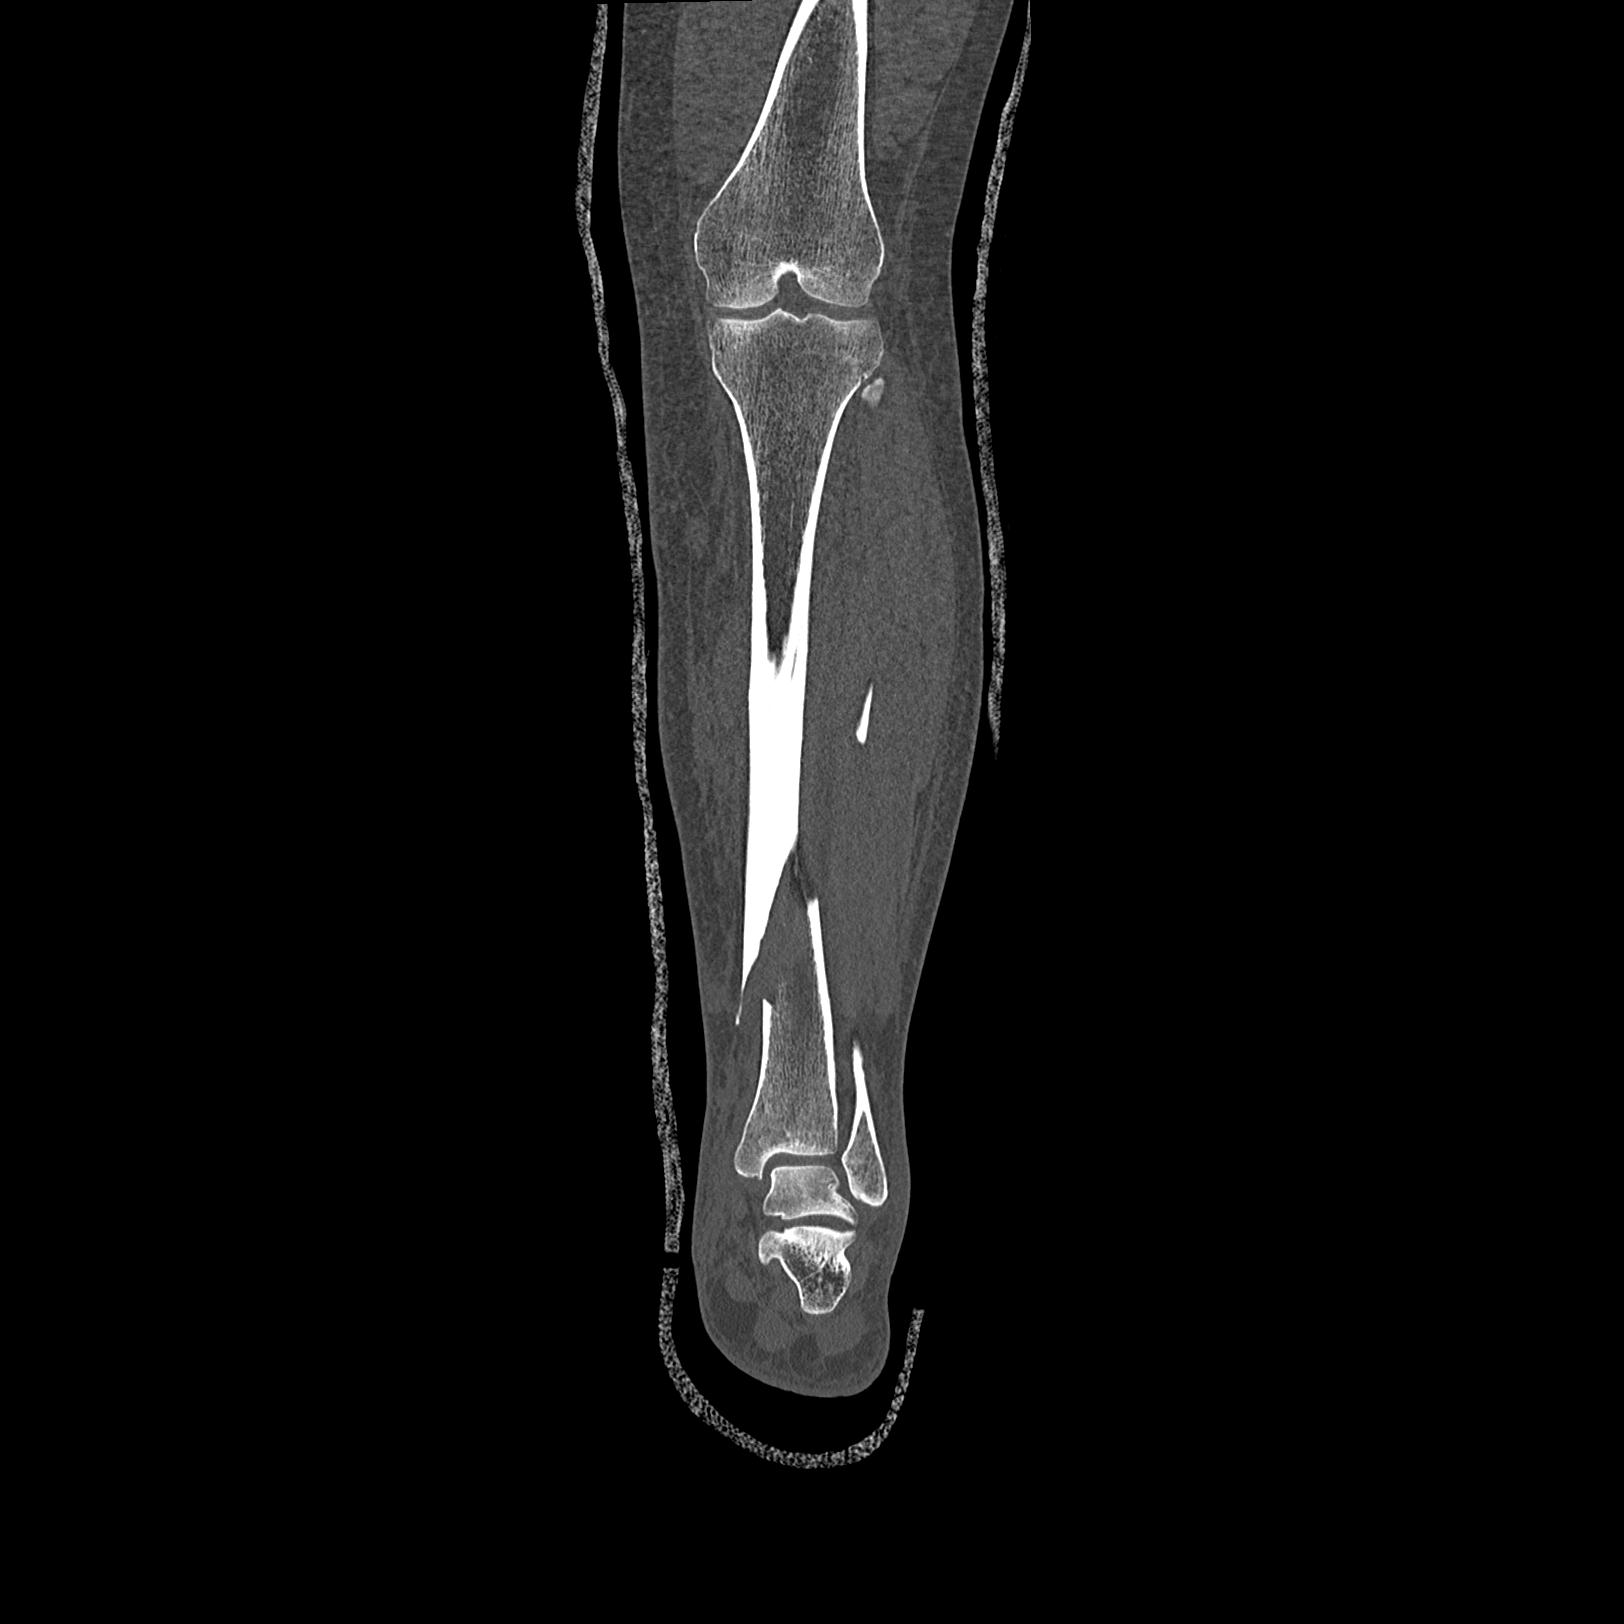

102803 1/12(キウスなし) 1/27 左下腿 4R 30歳女性 左脛骨軸内釘

110211 1/6 1/8 左前腕 4R 15歳男性 橈骨骨幹部骨折